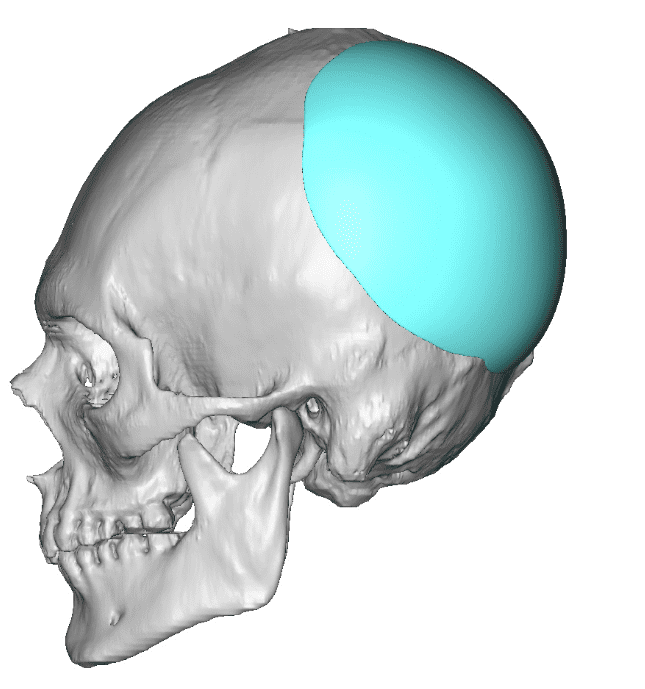

Desire for an improved head shape so that it looks rounder and not so peaked or sloped.

Placement of custom skull implant for parasagittal augmentation to create a rounder head shape. An example of what appears to be a high sagittal crest that is really low parasagittal skull areas.

Desire for an improved head shape so that it looks rounder and not so peaked or sloped.

Placement of custom skull implant for parasagittal augmentation to create a rounder head shape. An example of what appears to be a high sagittal crest that is really low parasagittal skull areas.